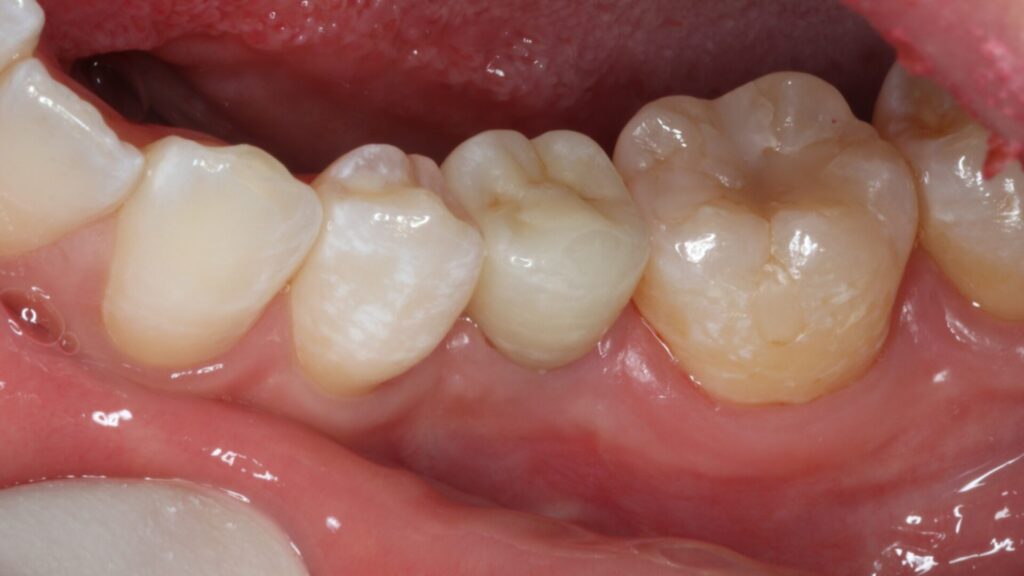

治療後

術後4ヵ月で最終的なセラミック冠を装着しています。

機能的にも見た目も満足いただける仕上がりになりました。

3か月後に仮歯を装着し、問題ないのを確認したうえでセラミック冠を装着し治療を終えました。